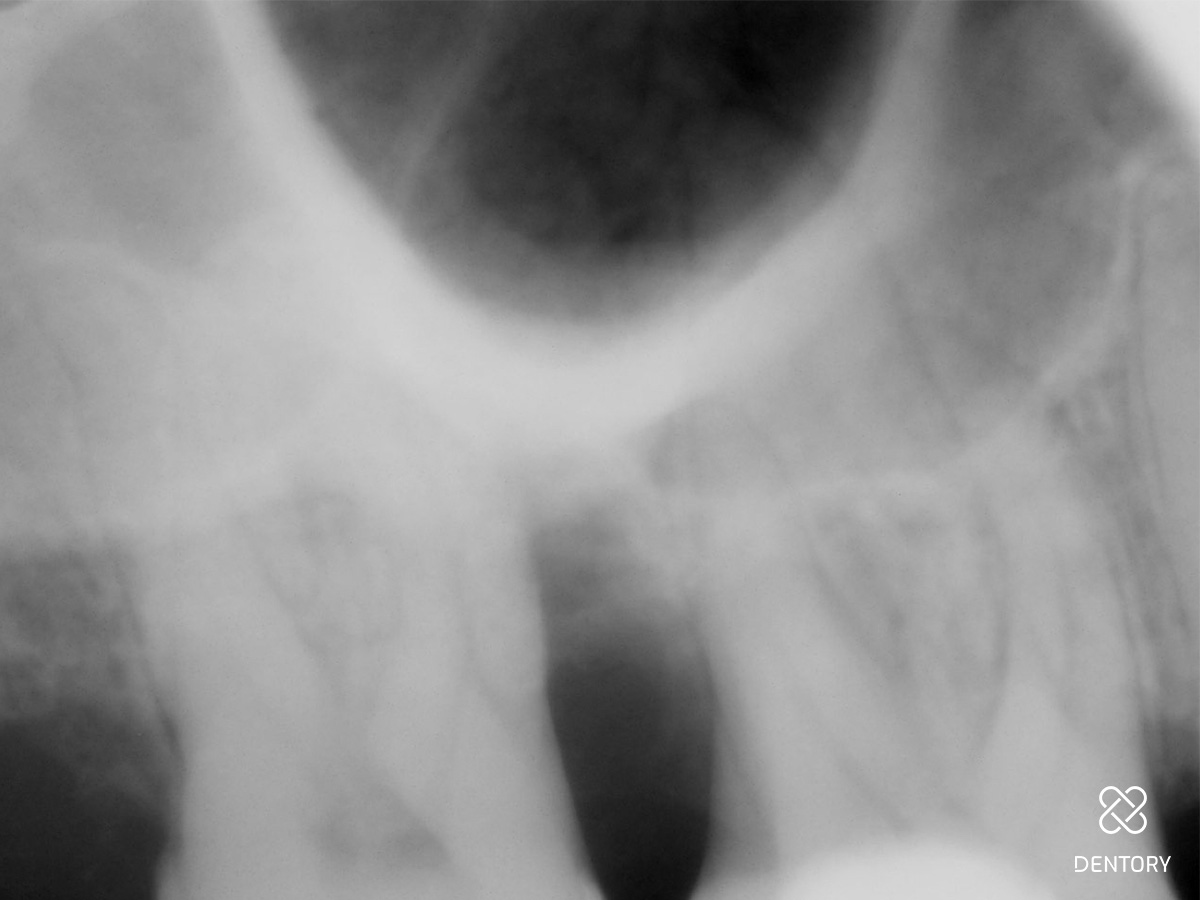

Abbildung 3

Das Röntgenbild weist einen vertikalen Knochendefekt an Zahn 17 mesial auf.